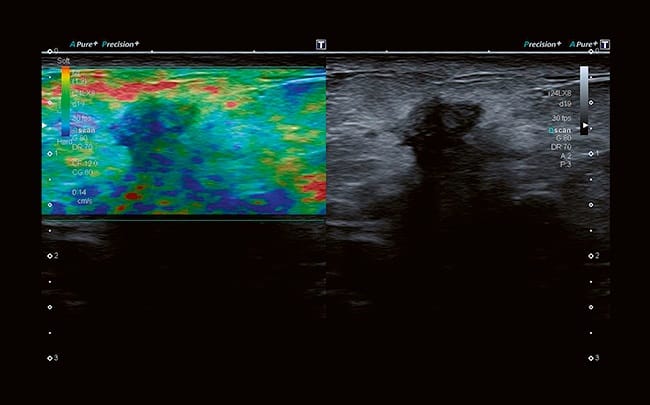

- Технология ApliPure+: многолучевое сканирование в реальном времени для повышения качества изображения

Компоненты ApliPure ™ + обеспечивают повышенную контрастность изображения и уменьшают спекл-шум для улучшения визуализации.

Технология Precision + позволяет получать однородные изображения, четкие углы и контуры.

Технология Superb Micro-vascular Imaging в сочетании с высокой частотой кадров повышает диагностическую достоверность при оценке микроциркуляторного русла за счет отображения низкоскоростного кровотока в микрососудах. Кроме того, данная технология незамен